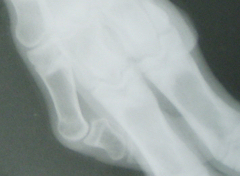

The Case of the Polydactyl Goat